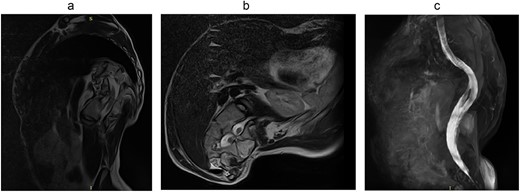

Magnetic resonance imaging (MRI) visualizes the separation of the spinal cord into two arms at the Th11 level (Fig. 5).